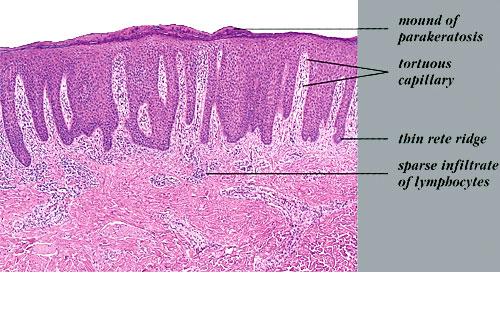

Psoriasis Vulgaris Histopathology The histologic picture of psoriasis vulgaris varies considerably with the stage of the lesion and usually is diagnostic only in early, scaling papules and near the margin of advancing plaques. |

The earliest pinhead-sized macules or smooth-surfaced papules show subtle histologic changes with a preponderance of dermal changes . At first, there is capillary dilation and edema in the papillary dermis, with a lymphocytic infiltrate surrounding the capillaries. The lymphocytes extend to the lower portion of the epidermis, where slight spongiosis develops. Then focal changes occur in the upper portion of the epidermis, where granular cells become vacuolated and disappear, and mounds of parakeratosis are formed. Neutrophils are usually seen only at the summits of some of the mounds of parakeratosis and appear scattered through an otherwise orthokeratotic cornified layer . These mounds of parakeratosis with neutrophils represent the earliest manifestation of Munro microabscesses . At this stage, which is characterized clinically by an early scaling papule, a histologic diagnosis of psoriasis can often be made. In some cases, when there is marked |

exocytosis of neutrophils, they may aggregate in the uppermost portion of the spinous layer to form small spongiform pustules of Kogoj. Lymphocytes remain confined to the lower epidermis, which, as more and more mitoses occur, becomes increasingly hyperplastic. The epidermal changes are at first focal, but later become confluent, leading clinically to plaques. In the fully developed lesions of psoriasis, as best seen at the margin of enlarging plaques, the histologic picture is characterized by (a) acanthosis with regular elongation of the rete ridges with thickening in their lower portion; (b) thinning of the suprapapillary epidermis with the occasional presence of small spongiform pustules; (c) pallor of the upper layers of the epidermis; (d) diminished to absent granular layer; (e) confluent parakeratosis; (f) the presence of Munro microabscesses; (g) elongation and edema of the dermal papillae; and (h) dilated and tortuous capillaries . |

The rete ridges show considerable elongation and extend downward to a uniform level, resulting in regular acanthosis . They are often slender in their upper portion but |

Munro microabscesses are located within the parakeratotic areas of the cornified layer . They consist of accumulations of neutrophils and pyknotic nuclei of neutrophils that have migrated there from capillaries in the papillae through the suprapapillary epidermis. As a rule, Munro microabscesses are easily found in early lesions but are few in number or absent in longstanding lesions . The dermal papillae, in accordance with the elongation and basal thickening of the rete ridges, are elongated and club shaped. They show edema, and the capillaries within them appear dilated and tortuous. A relatively mild inflammatory infiltrate is present in the upper dermis and the papillae. It consists of lymphocytes, except in early lesions, in which neutrophils are also present in the upper portion of the papillae . |